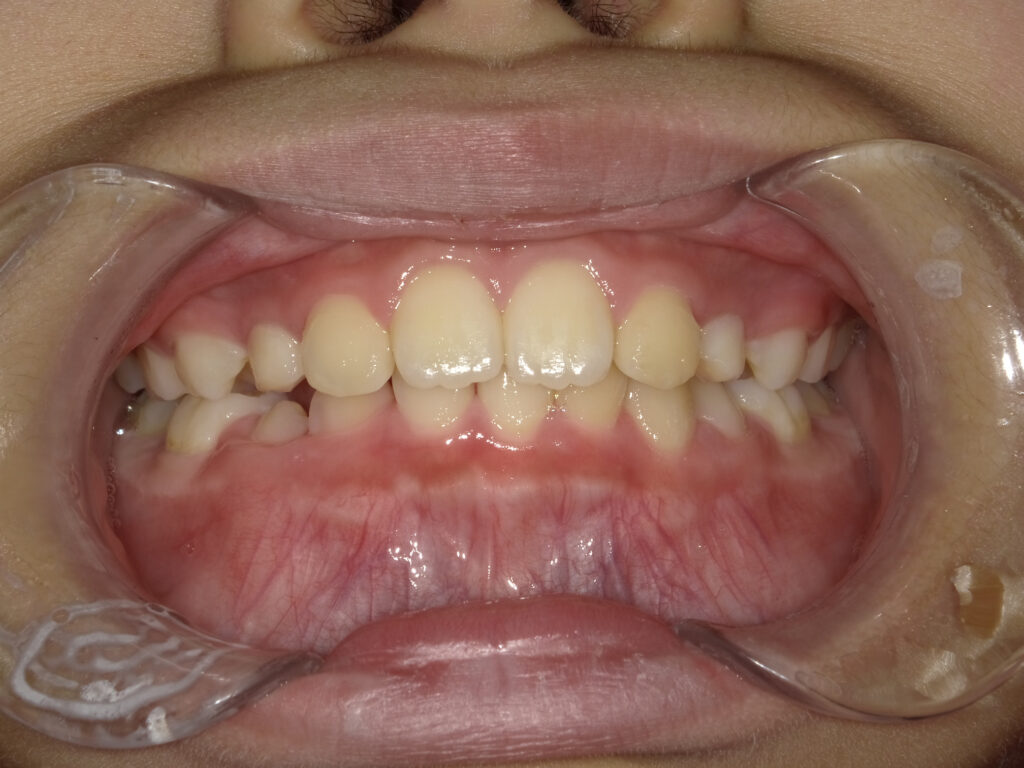

正面

治療前